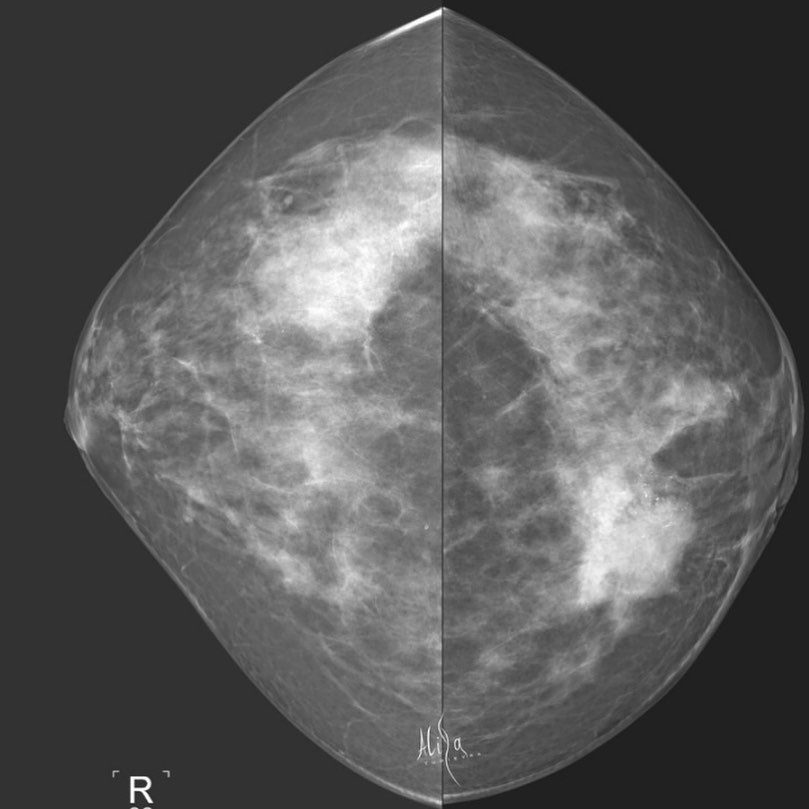

Женщина 1965гр Клинически - ЗН слева во внутреннем квадранте Маммография - синхронный рак Гистология: Инвазивная карцинома молочной железы G3. ⠀ Всё нашли?) наглядно и не сложно💚 #маммография #маммографияекб #диагностика #ракмолочнойжелезы #рентгенология #берегисебя #екатеринбург #синхронныйрак

Женщина 1965гр

Клинически - ЗН слева во внутреннем квадранте

Маммография - синхронный рак

Гистология:

Инвазивная карцинома молочной железы G3.